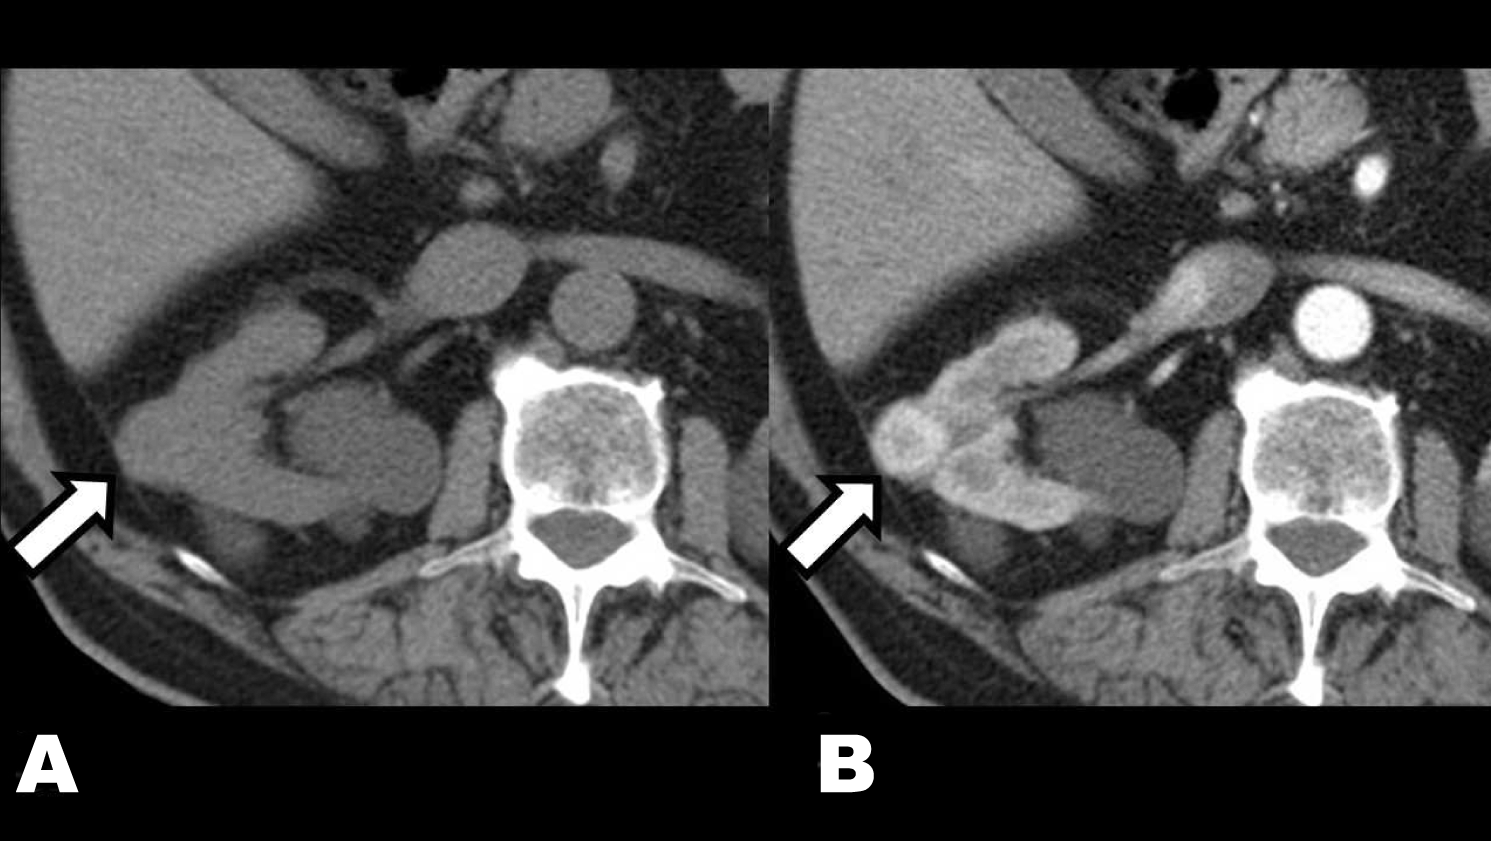

On February 2013, a 76-year-old male was sent to our nephrology unit to evaluate renal disease. He was asymptomatic and had been diagnosed with hypertension, overweight, benign prostatic hypertrophy and chronic obstructive pulmonary disease several years ago. His one daughter was also diagnosed with a renal cyst. His serum creatinine was 1.6 mg/dL, eGFR 42 mL/min, albumin/creatinine ratio in spot urine sample 2.8 mg/g and normal urinary sediment. Ultrasonography showed a slight enlargement of both kidneys and the presence of multiple bilateral cysts, predominantly with cortical distribution, classified as Bosniak I. No complex cysts that required monitoring or solid lesions were found (Figure 1). Therefore, he was diagnosed with Autosomal Dominant Polycystic Kidney Disease (ADPKD) and follow-up was drawn. He was successfully treated with losartan 50 mg/day. On July 2014, a new ultrasound control revealed the appearance of an echogenic nodule on the upper pole of the right kidney with vascularization in Doppler mode (Figure 2). The study was completed by computed tomography scan that confirmed the presence of a solid nodule of 23 mm on the right kidney with early contrast enhancement after i.v. iodine contrast administration. These findings strongly suggested the existence of superimposed renal cell carcinoma (RCC) (Figure 3). Considering his age and co-morbidities conservative treatment was planned.

Figure 3: (A) Computed tomography scan showing without intravenous contrast: exophytic isodense nodule compared to the rest of the renal parenchyma (white arrow), (B) Computed tomography scan in arterial phase after the administration of intravenous contrast: early enhancement predominates at the periphery of the nodule (white arrow).